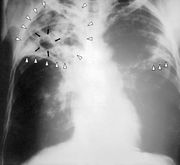

Tuberkulóza (z lat. tuberculum - hrbolek, nádorek), též TBC, dříve souchotiny, či úbytě (oubytě)[1], je bakteriální onemocnění způsobené bakteriemi Mycobacterium tuberculosis (tzv. Kochův bacil). Tuberkulóza je nejčastější příčinou smrti bakteriálního původu na světě.[2] V roce 2005 zemřelo ve světě na tuberkulózu 1,6 miliónu lidí, což odpovídá 4400 úmrtí na den.[3] Nejčastěji napadá plíce a projevuje se obvykle nespecifickými příznaky, jako je malátnost, hubnutí, kašel, nadměrné pocení a podobně. Potvrzuje se na základě rentgenového vyšetření a laboratorní kultivace či mikroskopická detekce původce tohoto onemocnění.